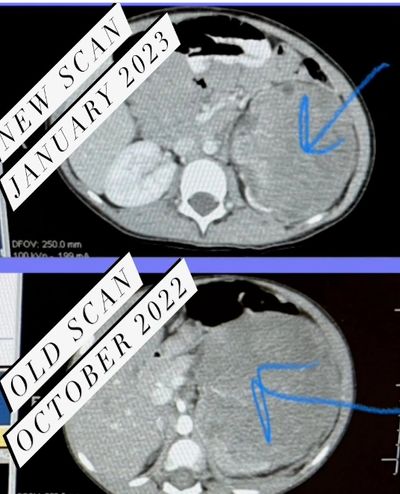

One week from her first visit to MD Anderson she started Chemo. She did weekly chemo for 10 weeks with ultrasounds, CT scans, and several other tests. Most weeks she tolerated Chemo well with little reactions and on occasion she felt sick and had other side effects. Her tumor has responded to treatments which is an answer to our prayers.

Here we are middle January 2023. She is scheduled to have her left kidney removed along with all of the cancer.